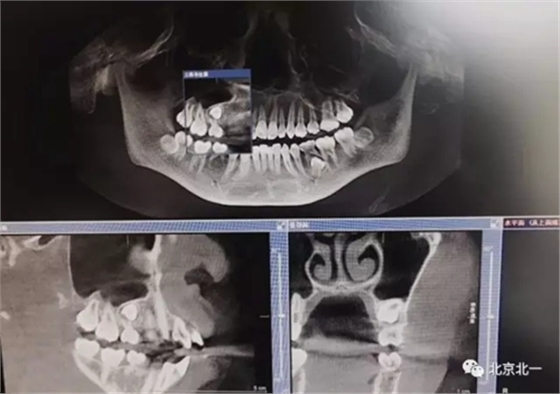

埋伏牙專用攪碎機攪碎牙齒